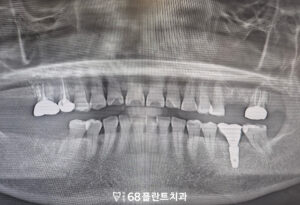

◆ 전 > 후 ◆

치료 마무리 후 사진입니다.

환자분께서는 치아의 금으로 인해

식사하기 힘들고 불편해 하셨으나

임플란트와 신경치료, 크라운 치료를 통해

저작 기능이 회복되면서

일상적인 식사에 불편함이 줄어들었고,

치료 결과에 대해 전반적으로 만족해 주셨습니다.

또한 살릴 수 있는 치아는

살리게 되어 다행이라며

좋아해 주셨습니다.